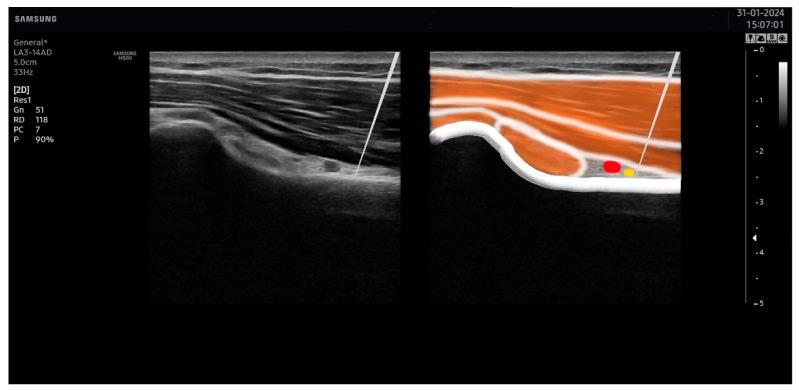

Percutaneous electrical nerve stimulation (PENS) appears to be effective for the treatment of musculoskeletal pain. The aim of this trial was to investigate the effects on disability and pain, as well as on the psychological aspects of adding PENS into an exercise program in patients with subacromial pain syndrome. A randomized, parallel-group clinical trial was conducted. Sixty patients with subacromial pain were allocated into exercise alone (n = 20), exercise plus PENS (n = 20), or exercise plus placebo PENS (n = 20) groups. Patients in all groups performed an exercise program twice daily for 3 weeks. Patients allocated to the PENS group also received four sessions of ultrasound-guided PENS targeting the axillar and suprascapular nerves. Patients allocated to the exercise plus placebo PENS received a sham PENS application. The primary outcome was related disability (Disabilities of the Arm, Shoulder, and Hand, DASH). Secondary outcomes included mean pain, anxiety levels, depressive symptoms, and sleep quality. They were assessed at baseline, one week after, and one and three months after. An analysis was performed using intention-to-treat with mixed-models ANCOVAs. : The results revealed no between-group differences for most outcomes (related disability: F = 0.292, = 0.748, n = 0.011; anxiety: F = 0.780, = 0.463, n = 0.027; depressive symptoms: F = 0.559, = 0.575, n = 0.02; or sleep quality: F = 0.294, = 0.747, n = 0.01); both groups experienced similar changes throughout the course of this study. Patients receiving exercise plus PENS exhibited greater improvement in shoulder pain at one month than those in the exercise (Δ -1.2, 95%CI -2.3 to -0.1) or the placebo (Δ -1.3, 95%CI -2.5 to -0.1) groups. The inclusion of four sessions of ultrasound-guided PENS targeting the axillar and suprascapular nerves into an exercise program did not result in better outcomes in our sample of patients with subacromial pain syndrome at one and three months after treatment.

经皮电神经刺激(PENS)似乎对治疗肌肉骨骼疼痛有效。本试验的目的是研究在肩峰下疼痛综合征患者中,将PENS添加到运动计划中对残疾和疼痛以及心理方面的影响。进行了一项随机平行组临床试验。60例肩峰下疼痛患者被分为单纯运动组(n = 20)、运动加PENS组(n = 20)或运动加安慰剂PENS组(n = 20)。所有组的患者每天进行两次运动计划,持续3周。分配到PENS组的患者还接受了针对腋神经和肩胛上神经的4次超声引导下的PENS治疗。分配到运动加安慰剂PENS组的患者接受假PENS治疗。主要结局是相关残疾(手臂、肩部和手部残疾,DASH)。次要结局包括平均疼痛、焦虑水平、抑郁症状和睡眠质量。在基线、治疗后1周、1个月和3个月时进行评估。采用意向性分析和混合模型协方差分析进行分析。结果显示,大多数结局在组间无差异(相关残疾:F = 0.292,P = 0.748,η² = 0.011;焦虑:F = 0.780,P = 0.463,η² = 0.027;抑郁症状:F = 0.559,P = 0.575,η² = 0.02;或睡眠质量:F = 0.294,P = 0.747,η² = 0.01);在本研究过程中,两组经历了相似的变化。与单纯运动组(Δ -1.2,95%CI -2.3至-0.1)或安慰剂组(Δ -1.3,95%CI -2.5至-0.1)相比,接受运动加PENS治疗的患者在1个月时肩部疼痛改善更大。在治疗后1个月和3个月时,将针对腋神经和肩胛上神经的4次超声引导下的PENS纳入运动计划,在我们的肩峰下疼痛综合征患者样本中并未产生更好的结局。